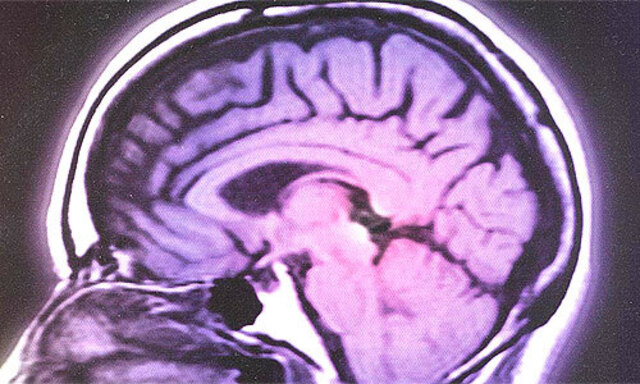

Hirnforschung: Für jeden Bekannten eine eigene Nervenzelle?

Neuronen können hoch spezialisiert sein – vor allem für das Erkennen von Gesichtern und Häusern.

Inzwischen scheint das nicht mehr so absurd. Natürlich ist nicht jede der über hundert Milliarden Neuronen im Gehirn für einen bestimmten Eindruck zuständig – das würde sich erstens gar nicht ausgehen, und zweitens überlappen Eindrücke bekanntlich –, aber etliche neue Arbeiten sprechen dafür, dass man die Rolle individueller Neuronen und ihrer Synapsen nicht unterschätzen sollte. So konnten Arthur Houweling und Michael Brecht (Berlin/Rotterdam) durch Stimulation einzelner Neuronen beeinflussen, ob eine Ratte auf einen Berührungsreiz reagierte oder nicht (Nature, online 20.12.).

Besonders viele spezialisierte Neuronen vermutet man im Gyrus fusiformis, hinter den Ohren: Dort sitzt die Erkennung von Gesichtern. Patienten mit Verletzungen dort leiden an Prosopagnosie, Gesichtsblindheit, sie erkennen Menschen nicht an ihren Gesichtern. Gleich nebenan liegt ein Areal, der Gyrus parahippocampalis, das besonders auf Gebäude anspricht. Wie stark sich die beiden Areale überschneiden, ist fraglich, auch, ob andere mit Emotionen behaftete Objekte ebenfalls dort repräsentiert sind. Immerhin fand man, dass der Gyrus fusiformis bei Vogelkundlern aktiv ist, wenn sie einen Vogel sehen, bei Autonarren, wenn sie ein Auto erkennen. Könnten auch Wörter dort repräsentiert sein? Das ist gar nicht leicht zu untersuchen, da deren Bedeutung in den Sprachzentren immense Aktivität auslöst, die den Effekt überlagern.

Das menschliche Hirn enthält über 100 Milliarden Nervenzellen (Neuronen), manche Schätzungen gehen bis zu einer Billion. Ein Neuron ist mit bis zu 10.000 anderen Neuronen via Synapsen verbunden.